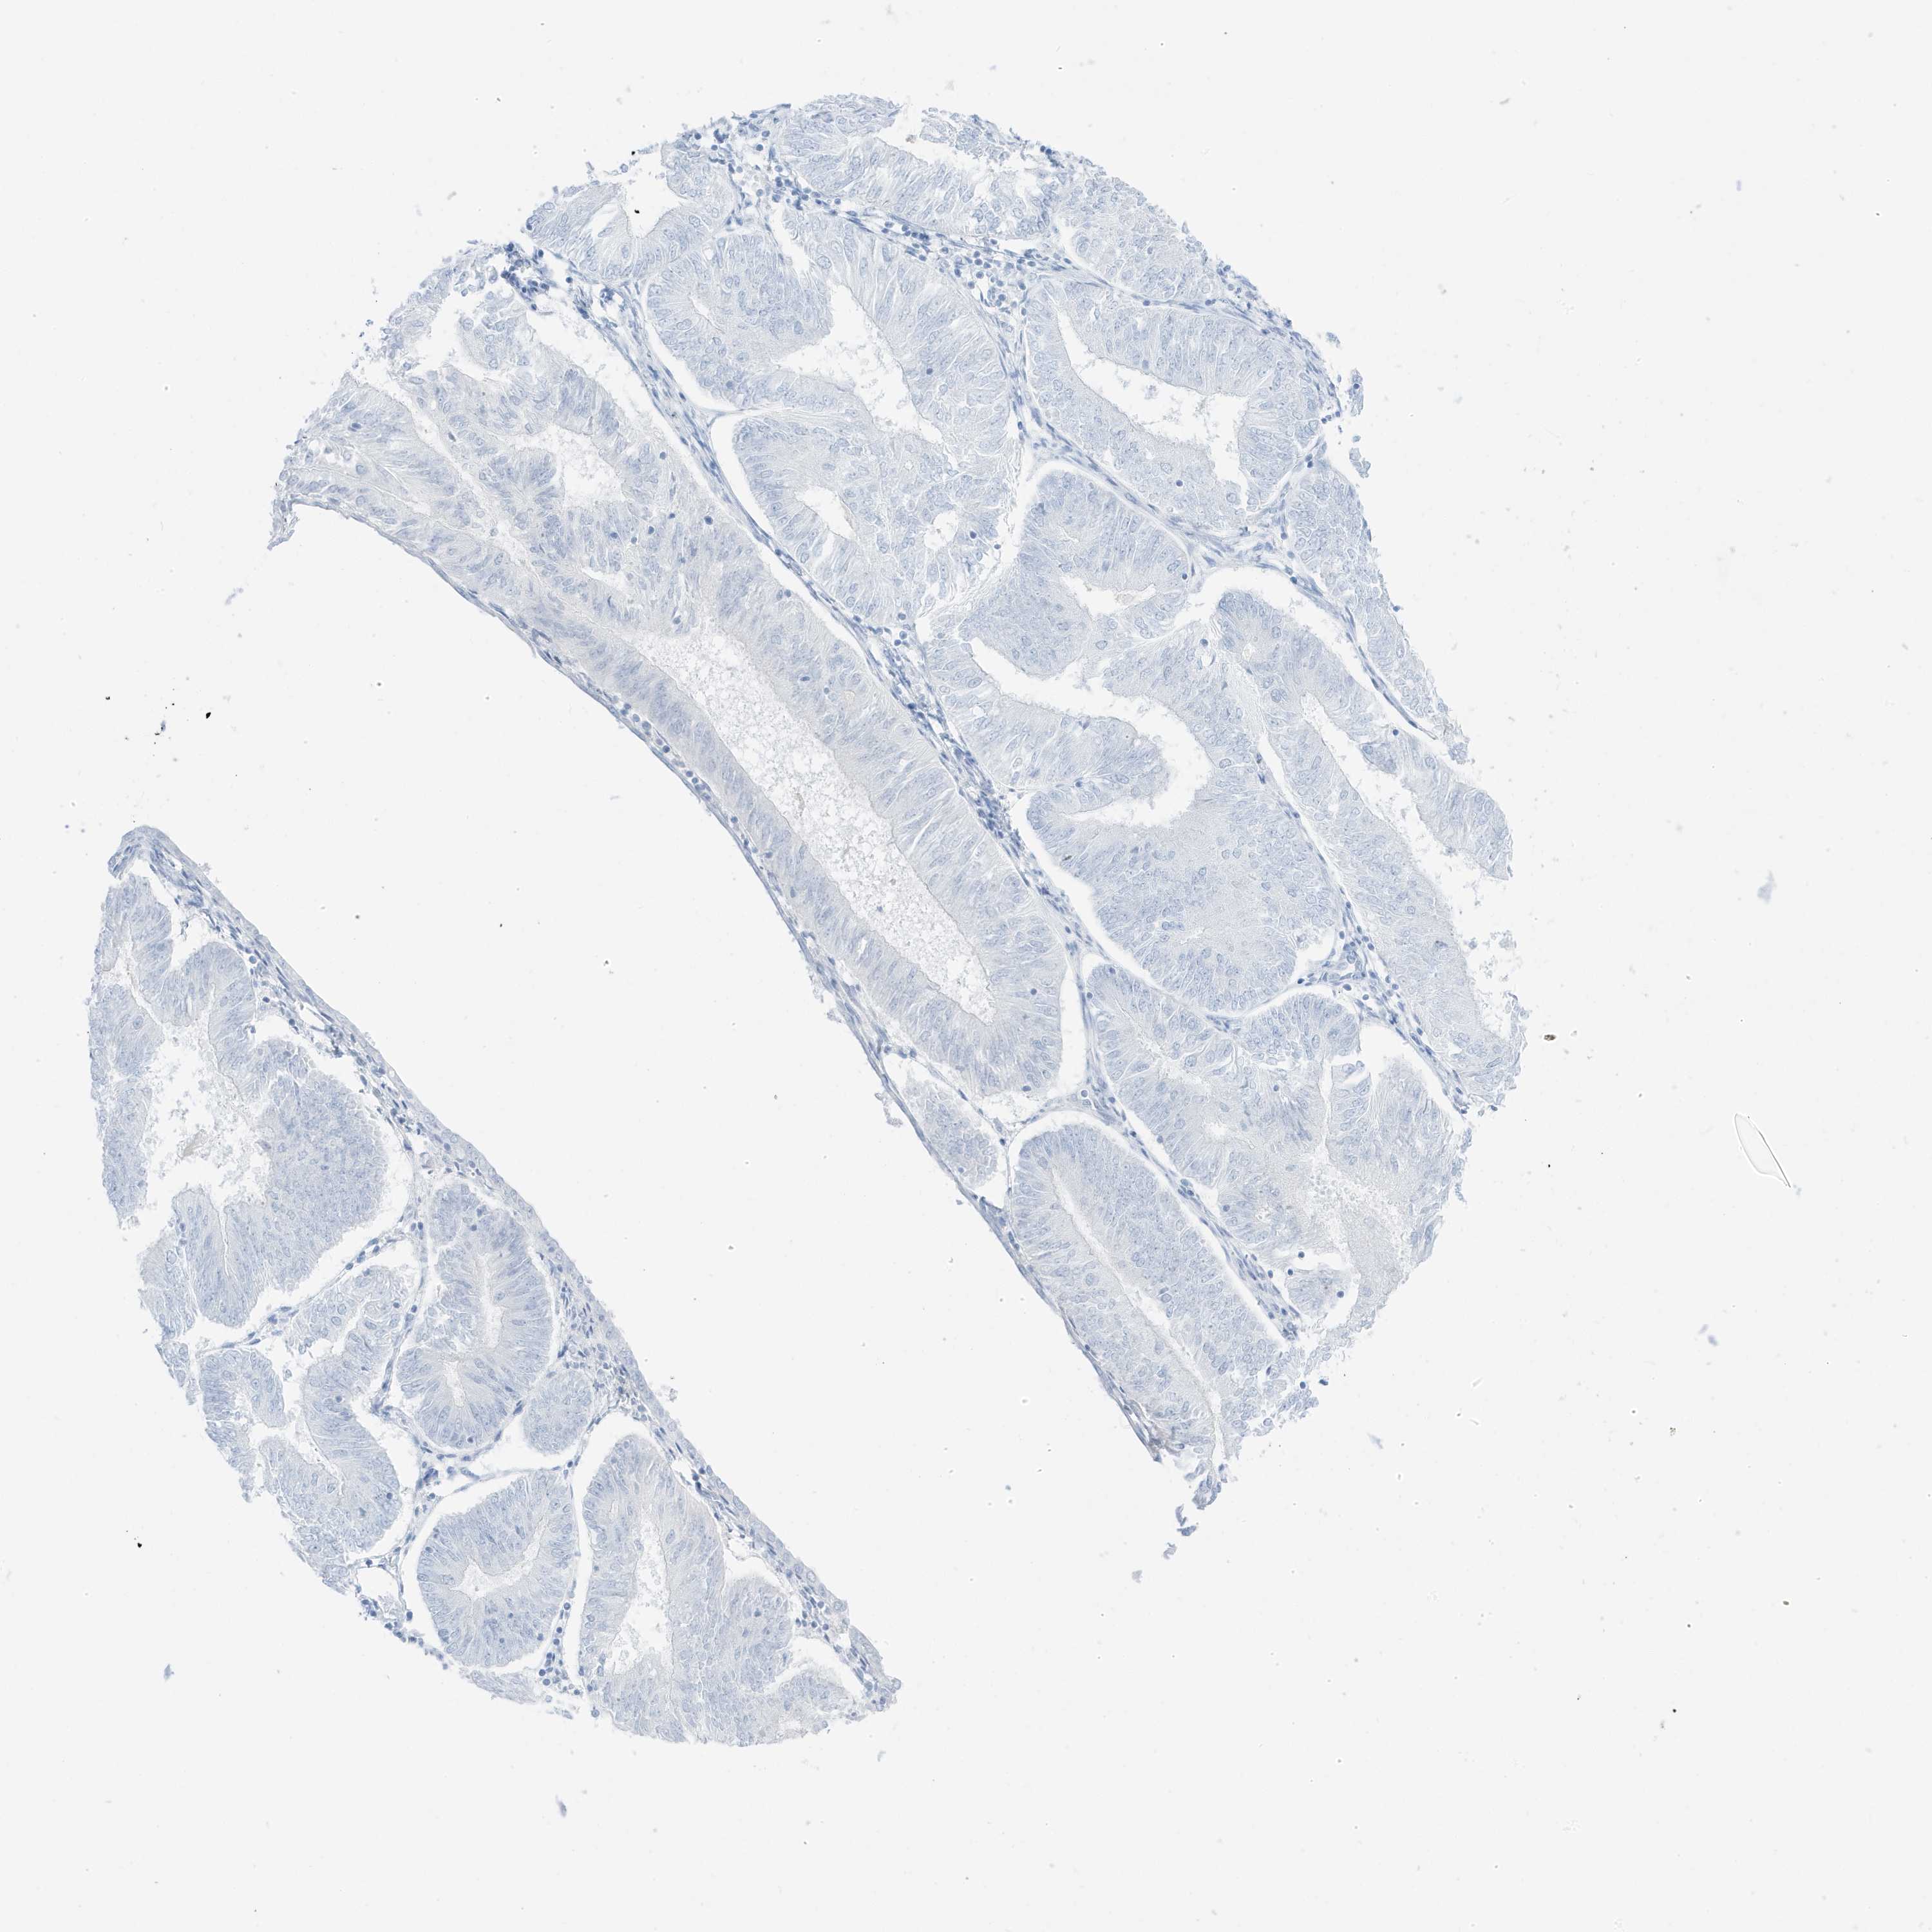

ENDOMETRIAL CANCER - Protein expressioni

A mouse-over function shows sample information and annotation data. Click on an image to view it in a full screen mode. Samples can be filtered based on level of antibody staining by selecting one or several of the following categories: high, medium, low and not detected. The assay and annotation is described here.

Note that samples used for immunohistochemistry by the Human Protein Atlas do not correspond to samples in the TCGA dataset.

Antibody stainingi

Antibody staining in the annotated cell types in the current human tissue is reported as not detected, low, medium, or high, based on conventional immunohistochemistry profiling in selected tissues. This score is based on the combination of the staining intensity and fraction of stained cells.

Each image is clickable and will lead to virtual microscopy that enables deeper exploration of all samples and also displays staining intensity scores, fraction scores and subcellular localization as well as patient and tissue information for each sample.

Antibody HPA035603

Antibody HPA035962

Staining

High

Medium

Low

Not detected

Intensity

Strong

Moderate

Weak

Negative

Quantity

>75%

75%-25%

<25%

None

Location

Nuclear

Cytoplasmic/membranous

Cytoplasmic/membranous,nuclear

Adenocarcinoma, NOS

Adenocarcinoma, metastatic, NOS